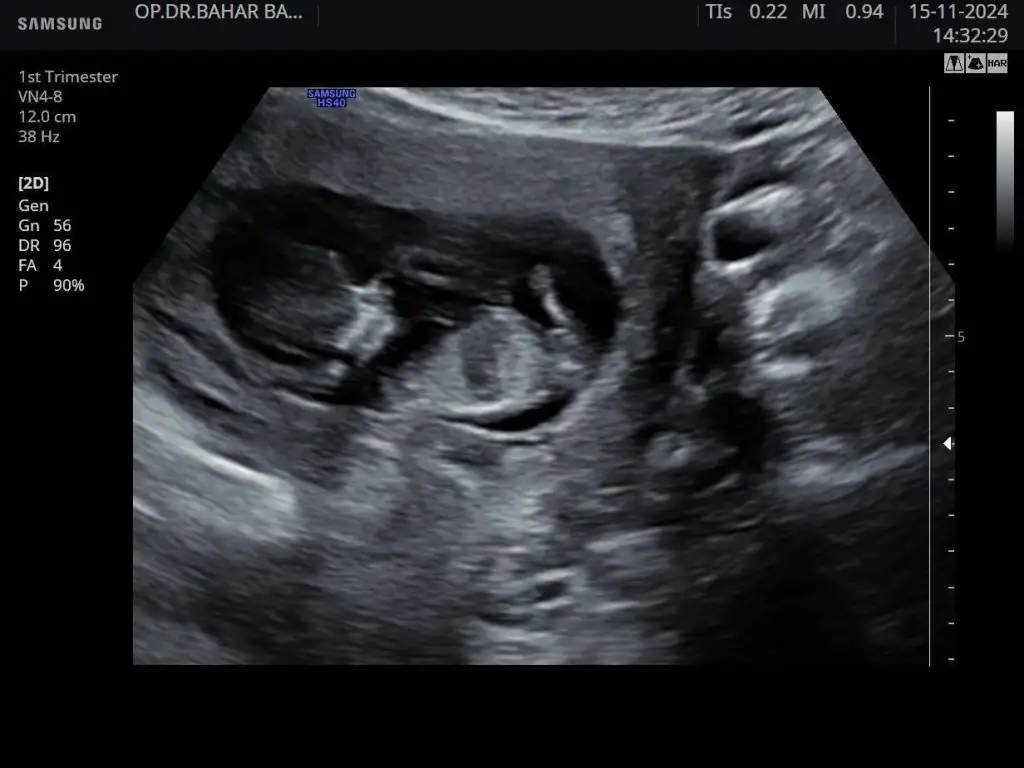

12 haftalık. Doktor bir tahminde bulundu. Kız gibi ama üstten bacak arasına da bakayım dedi üstten bir türlü göremedi. Alt popo tarafından açtı ayağını arası boş dedi. Ama daha küçük 1-2 haftaya netleşir dedi.

Merhaba 10 haftalık cinsiyet tahmini yapabilir misiniz rica etsem

• IMG-20241128-WA0014.webp

IMG-20241128-WA0014.webp

21,7 KB · Görüntüleme: 32

• IMG-20241128-WA0011.webp

IMG-20241128-WA0011.webp

31,8 KB · Görüntüleme: 31

• IMG-20241128-WA0008.webp

IMG-20241128-WA0008.webp

19,4 KB · Görüntüleme: 37